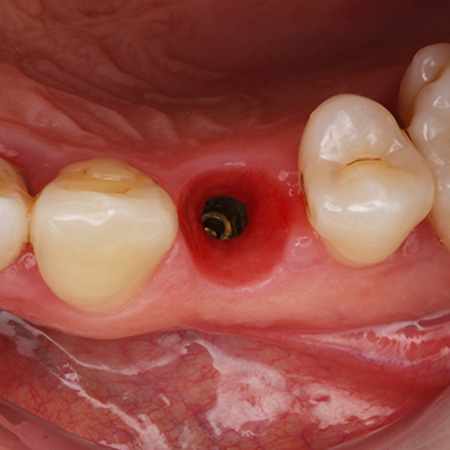

Fig. 04 : situation clinique à J0 (lors de la pose de la couronne provisoire transvissée) vue vestibulaire, vue latérale et vue occlusale.